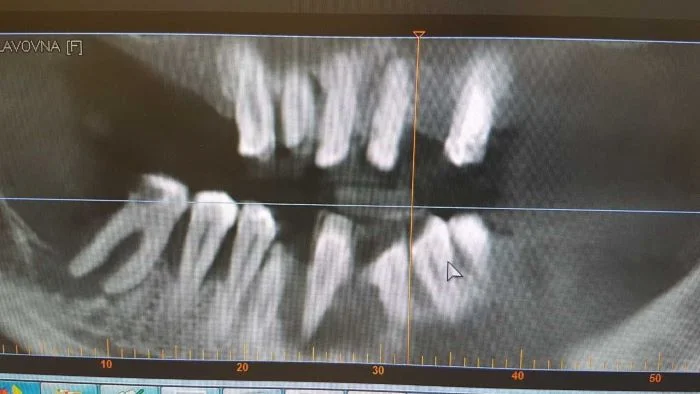

Тяжелая степень пародонтита

Пародонтит, тяжелая степень. Важно понимать, что пародонтит достаточно медленное заболевание. Развиваться он может годами, но самое неприятное - протекает он практически бессимптомно. Пациент просто приходит в один прекрасный день и теряет по 5-10 зубов. Поэтому посещение пародонтолога и гигиена раз в 6 месяцев необходимы всем и каждому.